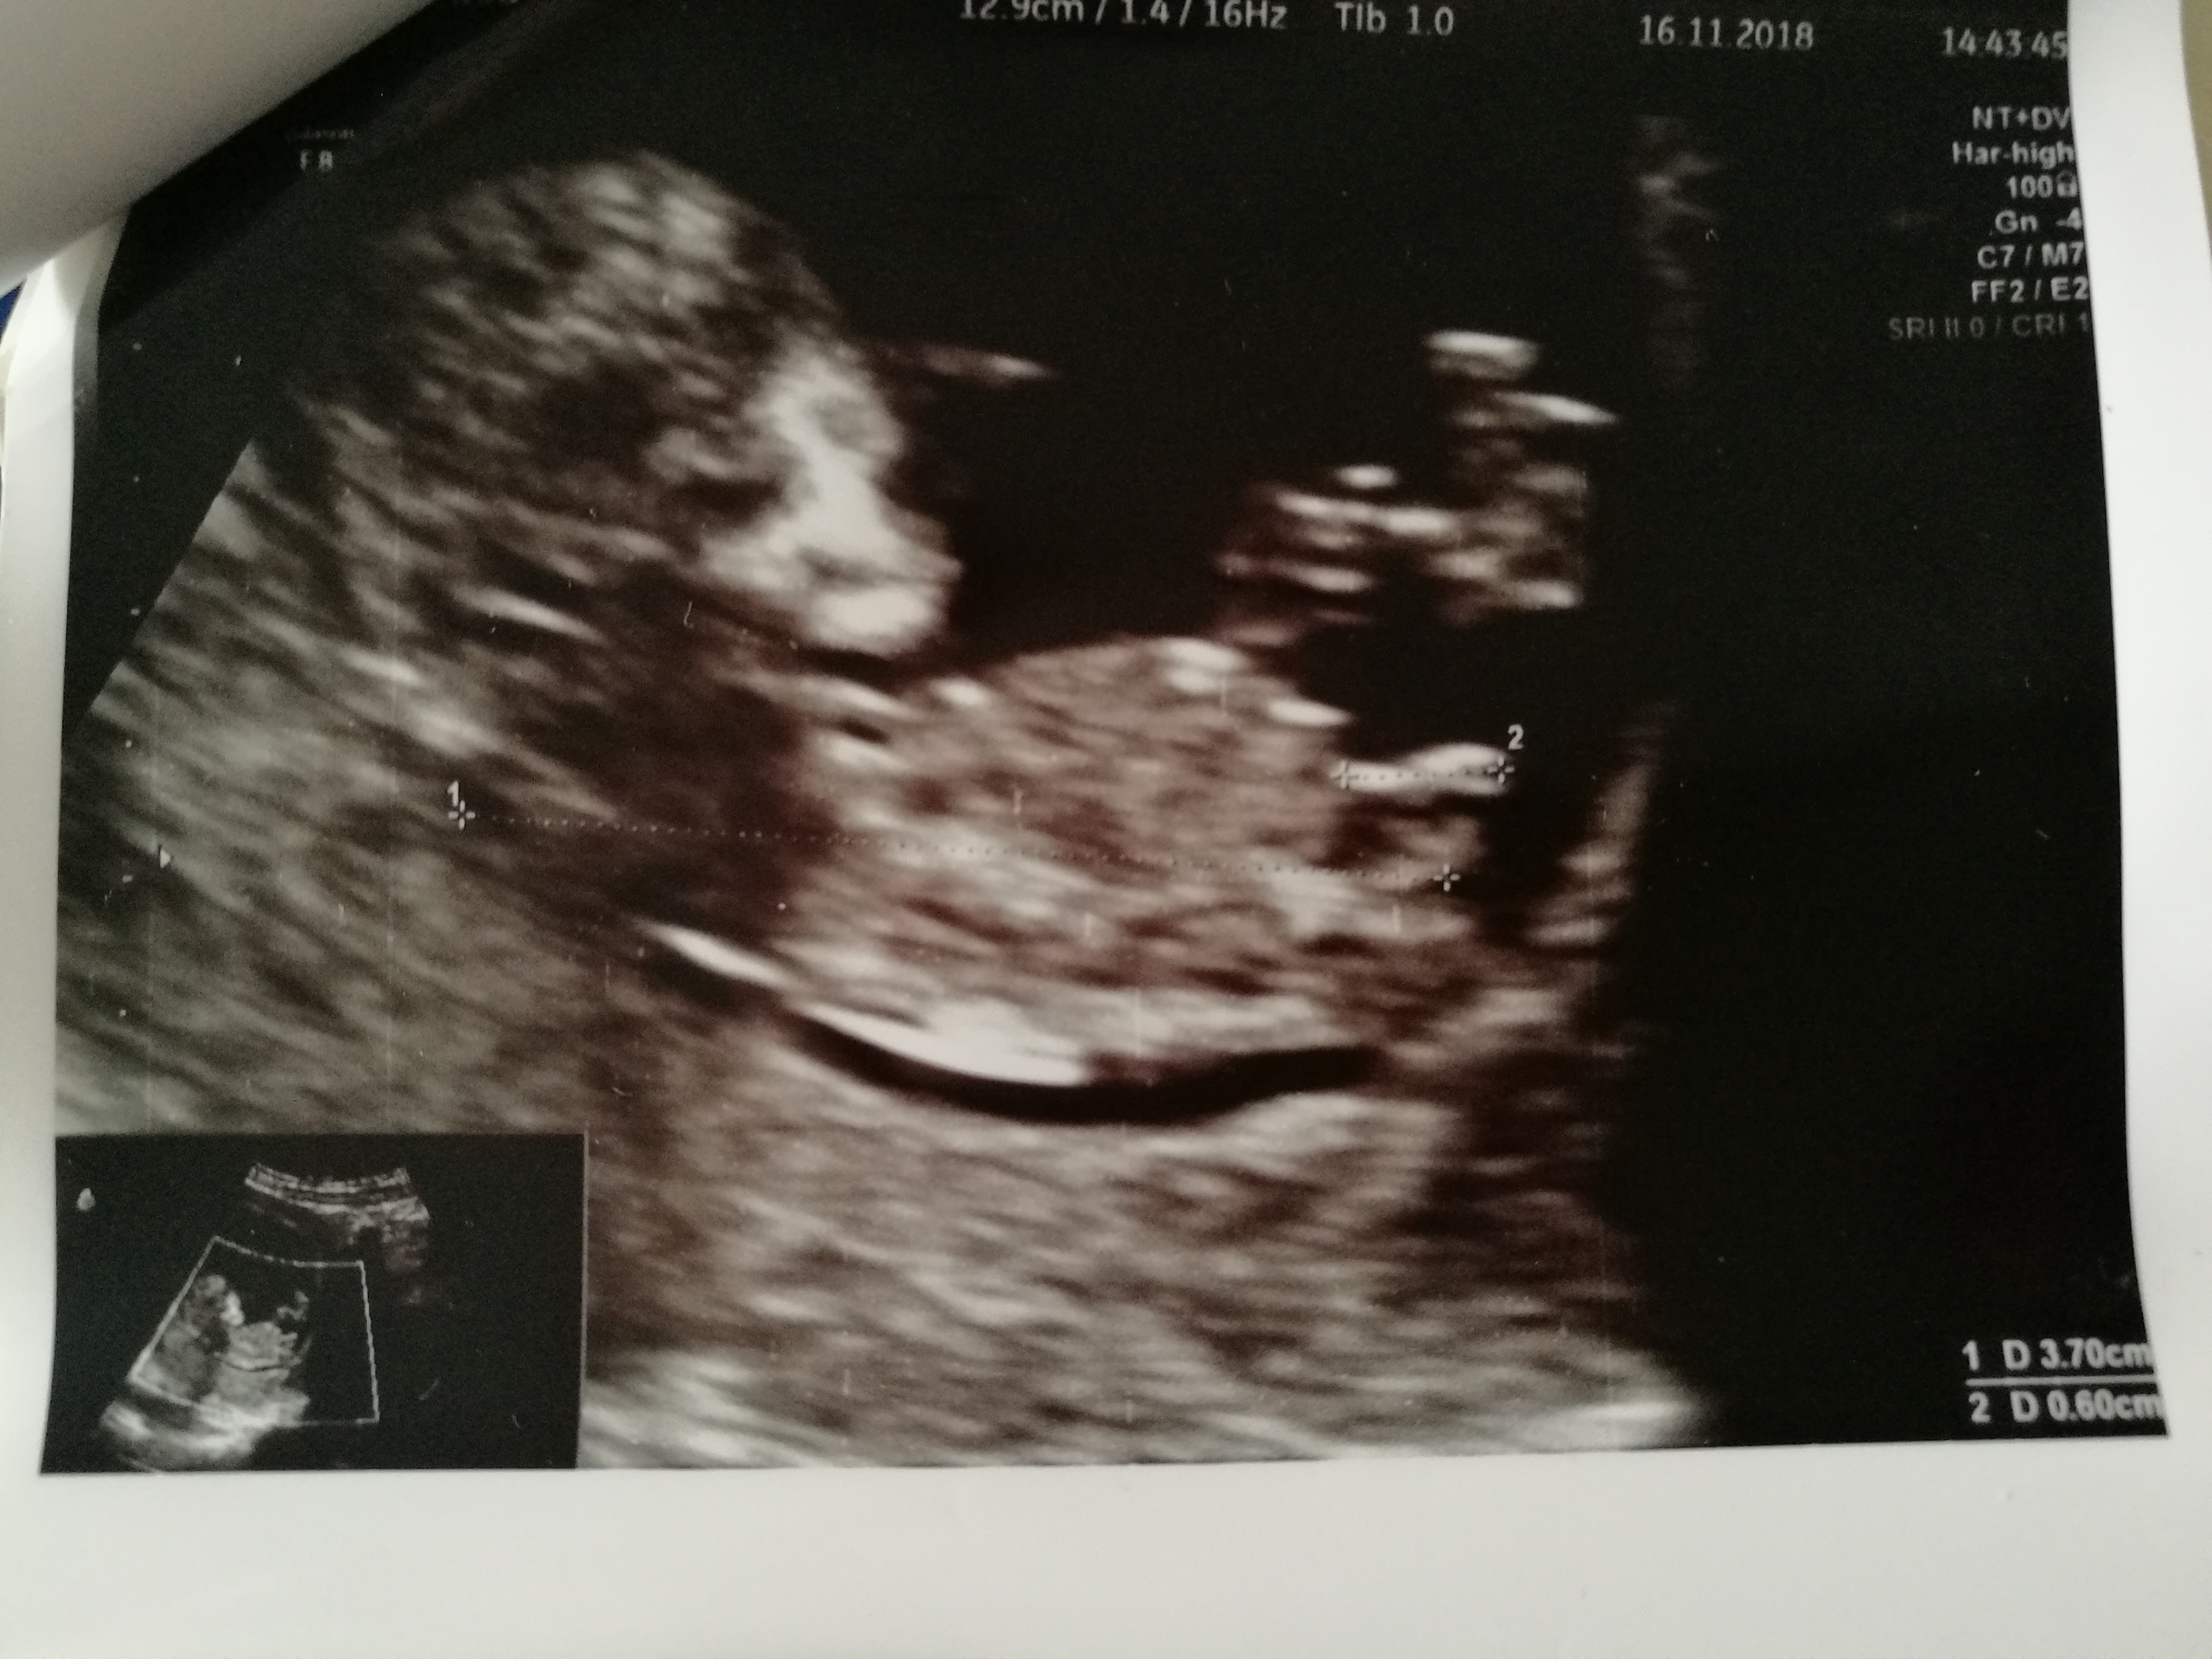

Witam w 19 tygodniu ciąży dowiedziałam się ze będę miała dziewczynkę w 20 tyg okazało się jednak , że to chłopak. Sama już nie wiem bo na jednym usg widać na pewno dziewuche a na drugim chłopca. Może to pempowina ?? Może ktoś mi pomoże rozwiązać ta zagadkę

Cześć dziewczyny. Co sądzicie o moich zdjęciach? W 11tc5dc pierwsze zdj-lekarz stwierdził że na 75prc. dziewczynka. Tydzien później jeszcze raz byłam u niego, bo jeszcze musiał coś podejrzeć i w 12tc5d następne zdjęcia-powiedział że dziś na 75 prc. chłopak. Powiedział ogólnie że daje 50proc i trzeba poczekać do połówkowego. Czy ktoś miał tak szybką zmianę płci. Zdjęcia z obydwu badań wydają się jednoznaczne: na pierwszym dziewczynka, na drugim chłopiec. Czy już zostanie chłopiec?? Czy jest szansa że się zmieni? Ktoś tak miał? Dałybyście 100proc chłopak, czy jakąś nadzieję na dziewczynkę? Lekarz uznał, że jest jakiś procent kobiet u których się to zmienia, nie wiem co miał na myśli.